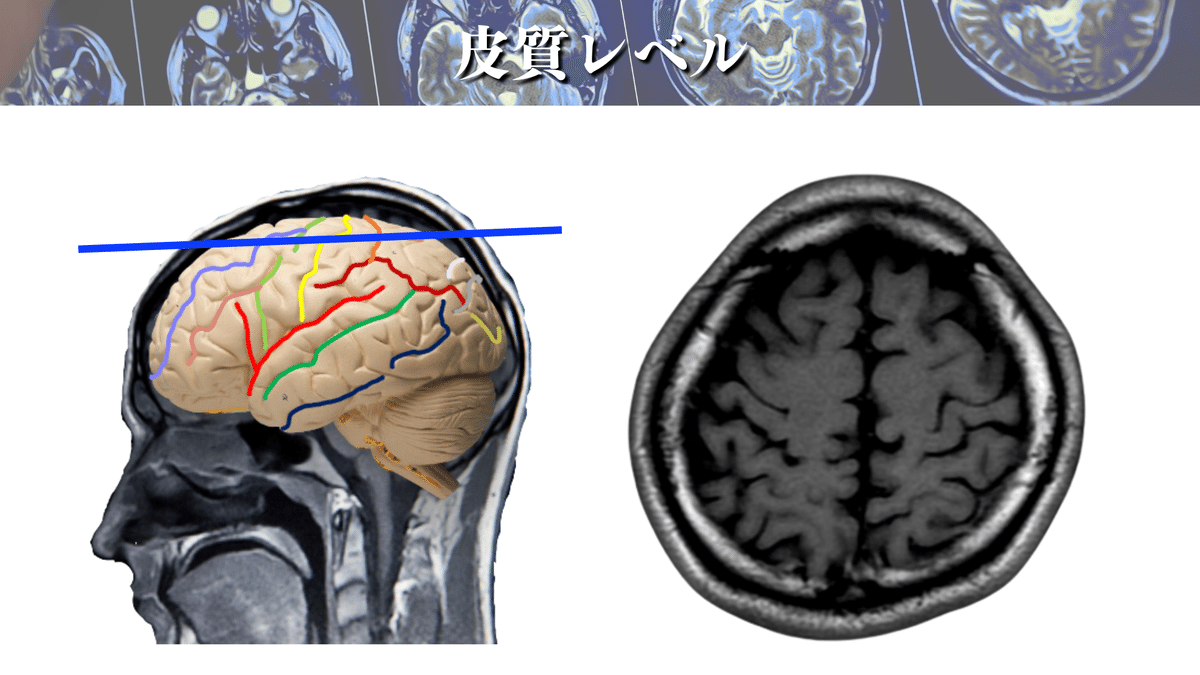

皮質レベル

上図からM1を探すことはできますか?🕵️♀️

できなかった場合も安心してください☺️

これから1つづつ解説していきますよ👍

M1を探すなら、まずは「中心溝」を探しましょう!

なぜなら、M1は中心前回に位置しており、中心前回は中心溝の前にある脳回だからその名前がついています👍